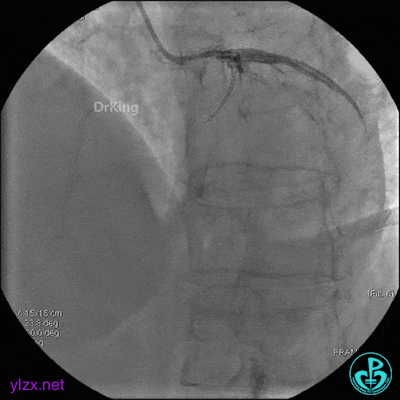

4 急诊冠脉造影

左主干轻度狭窄,左主干到前降支近端钙化影明显。前降支开口严重狭窄,近端闭塞。粗大回旋支轻度狭窄。

右冠脉无严重狭窄,右冠脉没有给前降支提供逆向供血。